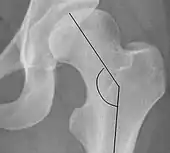

| Sharp angle | ![]() |

Acetabular slope | <45°

|